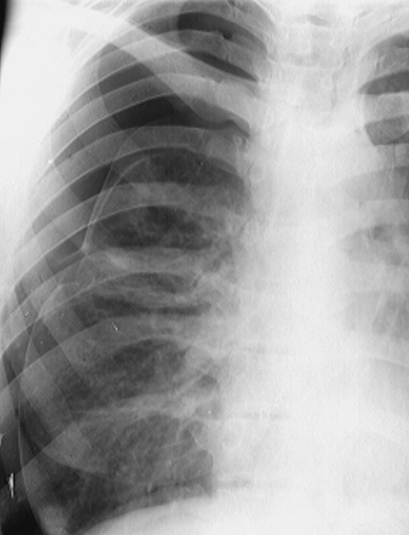

Rx toracică, incidență P-A

DESCRIERE:

la niv. întregului hemitorace stg → opacitate extinsă, nesistematizată, de intensitate mare, omogenă

caracter retractil → tracționează traheea și mediastinul de partea afectată

fără bronhogramă aerică

duce la micșorarea spațiilor intercostale

la niv. hemitoracelui controlateral → hipertransparență compensatorie (emfizem)

DX: atelectazie prin NBP central endobronșic (pe bronhia principală stg)

DD: pleurezie masivă → caracter expansiv